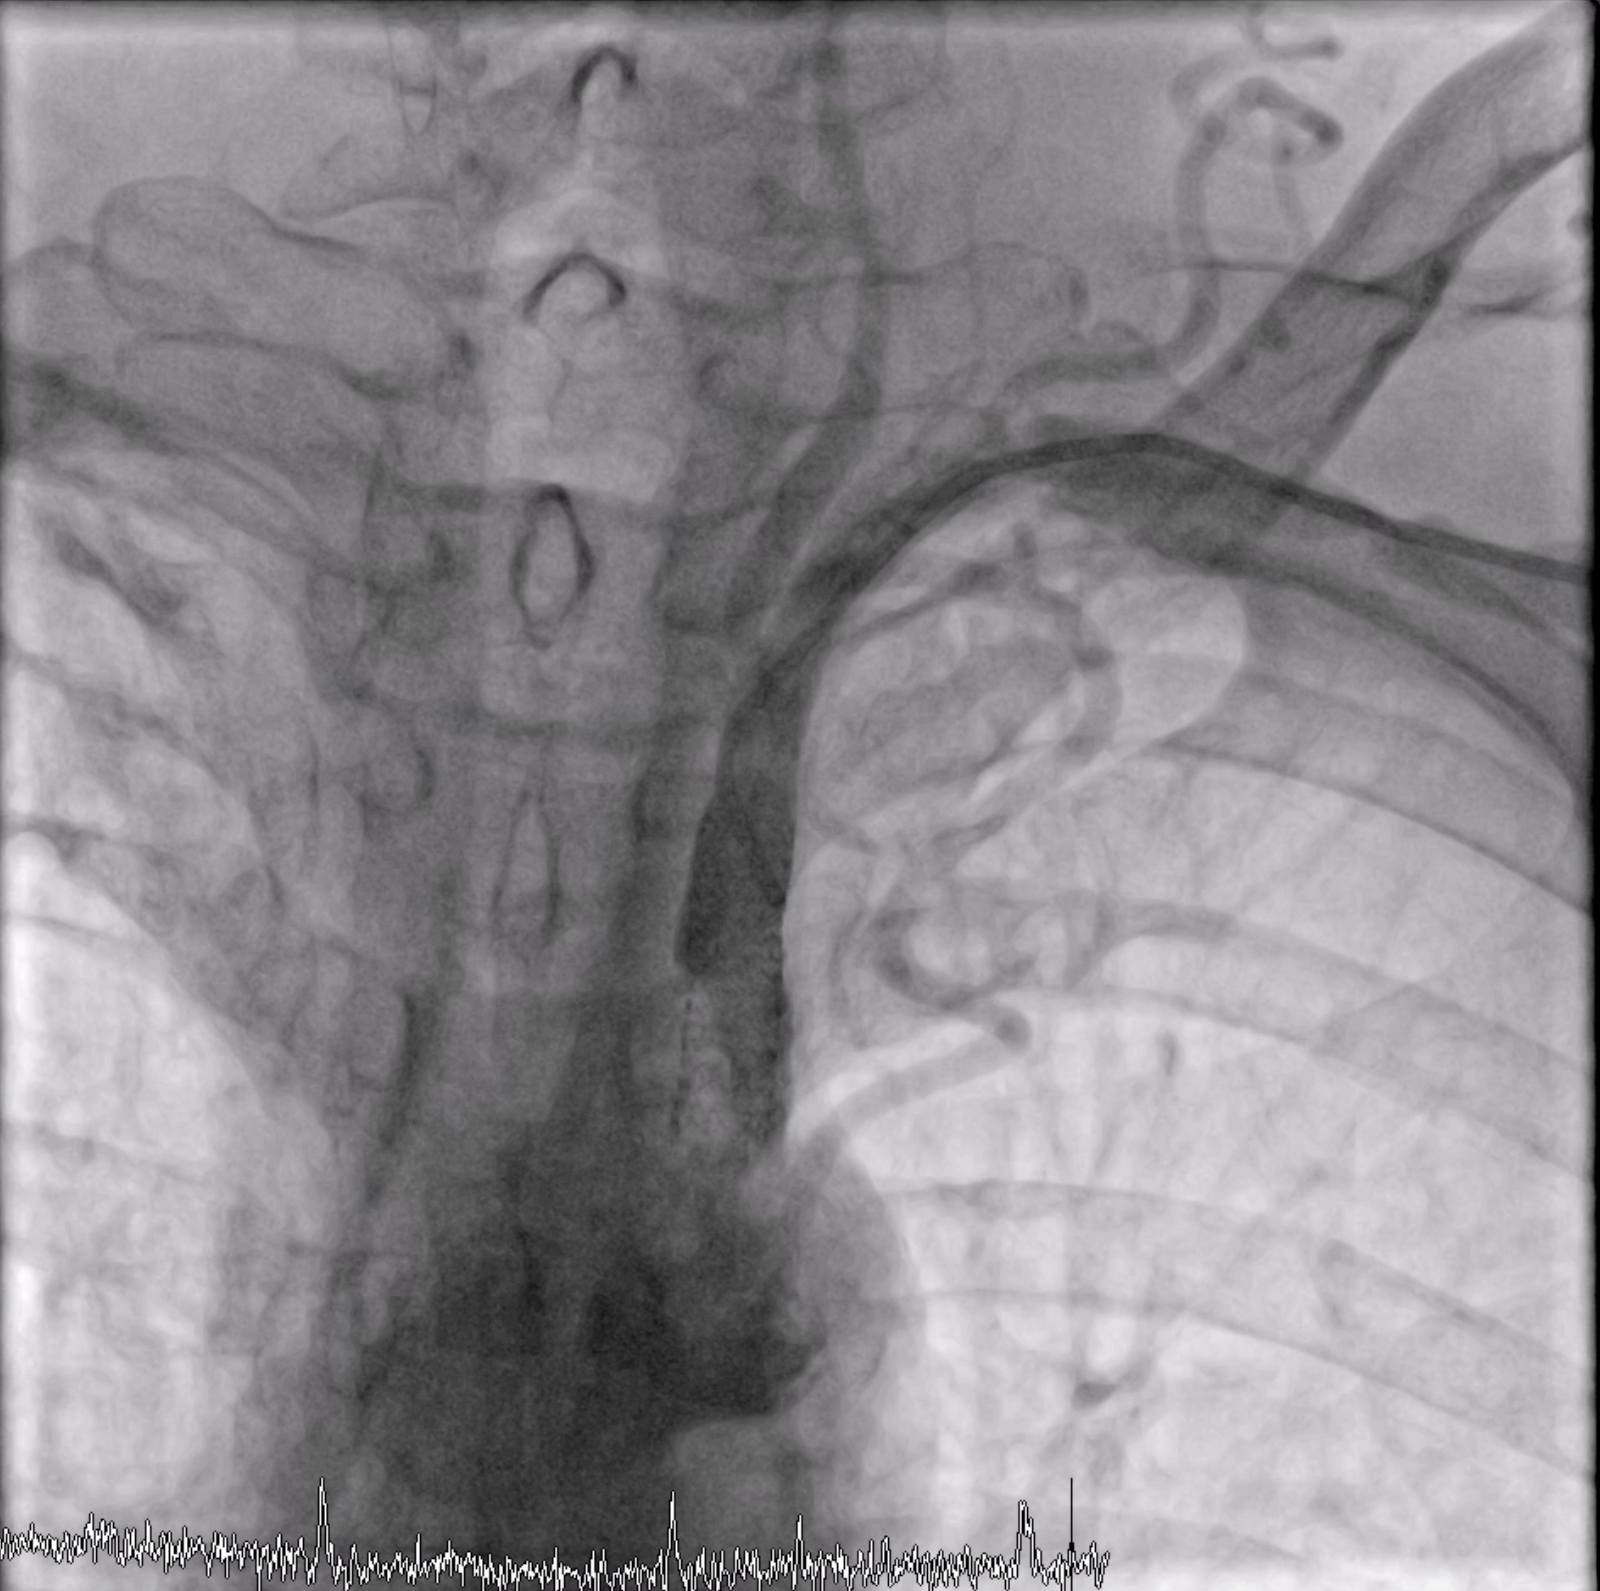

After we performed cine-angiography of the left subclavian artery using AP view, we drew the upper and lower border of the stenosis location with permanent marker on the machine¡¯s screen. We decided not to use a guiding catheter to intervene the left subclavian stenosis. Using JR 4.0 diagnostic catheter, we inserted 0.035¡± PTFE J tip guide wire 150 cm into the left subclavian artery, crossed the lesion, and secured distally into the aorta.We pulled out the JR 4.0 diagnostic catheter, then we delivered a MustangTM Balloon Dilatation Catheter (Boston Scientific) 5.0 x 40 mm into the lesion. We positioned the Mustang balloon according to the ¡®mark¡¯ that we made in the screen, then inflated it.After pre-dilating with the balloon, next we delivered ExpressTM Vascular LD Stent (Boston Scientific) 8.0 x 27 mm into the lesion (according to the ¡®mark¡¯) and deployed the stent. After that, we advanced the balloon stent about 3-4 mm further and post-dilated the stent.The final result was good with no residual stenosis and no dissection.

Case Summary

We successfully performed PTA stent placement in the subclavian artery via left radial artery access without a guiding catheter. This "running naked" procedure was possible as long as we could maintain a stable position during balloon dilatation and stent deployment. There would be a risk of plaque embolization in this procedure, but this complication did not occur in this patient.